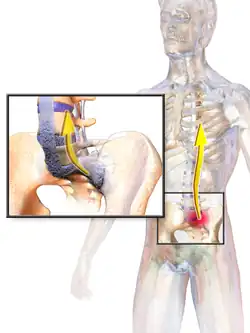

Ankylosing spondylitis (AS) is a type of arthritis from the disease spectrum of axial spondyloarthritis.[5] It is characterized by long-term inflammation of the joints of the spine, typically where the spine joins the pelvis.[2] With AS, eye and bowel problems—as well as back pain—may occur.[2] Joint mobility in the affected areas sometimes worsens over time.[2][6] Ankylosing spondylitis is believed to involve a combination of genetic and environmental factors.[2] More than 90% of people affected in the UK have a specific human leukocyte antigen known as the HLA-B27 antigen.[7] The underlying mechanism is believed to be autoimmune or autoinflammatory.[8] Diagnosis is based on symptoms with support from medical imaging and blood tests.[2] AS is a type of seronegative spondyloarthropathy, meaning that tests show no presence of rheumatoid factor (RF) antibodies.[2]

AS can occur in any part of the spine or the entire spine, often with pain localized to either buttock or the back of the thigh from the sacroiliac joint. Arthritis in the hips and shoulders may also occur. When the condition presents before the age of 18, AS is more likely to cause pain and swelling of large lower limb joints, such as the knees.[13] In prepubescent cases, pain and swelling may also manifest in the ankles and feet where heel pain and enthesopathy commonly develop.[13] Less common occurrences include ectasia of the sacral nerve root sheaths.[14]

"Bamboo spine" develops when the outer fibers of the fibrous ring (anulus fibrosus disci intervertebralis) of the intervertebral discs ossify, which results in the formation of marginal syndesmophytes between adjoining vertebrae.